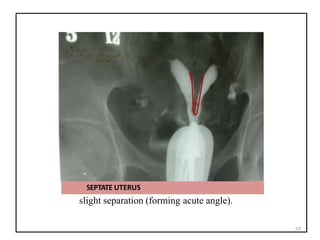

SEPTATE UTERUS: PARTIAL AND

COMPLETE

There is incomplete resorption of the final fibrous

septum between the two uterine horns.

SEPTUM

PARTIAL COMPLETE

SEPTATE UTERUS

slight separation (forming acute angle).